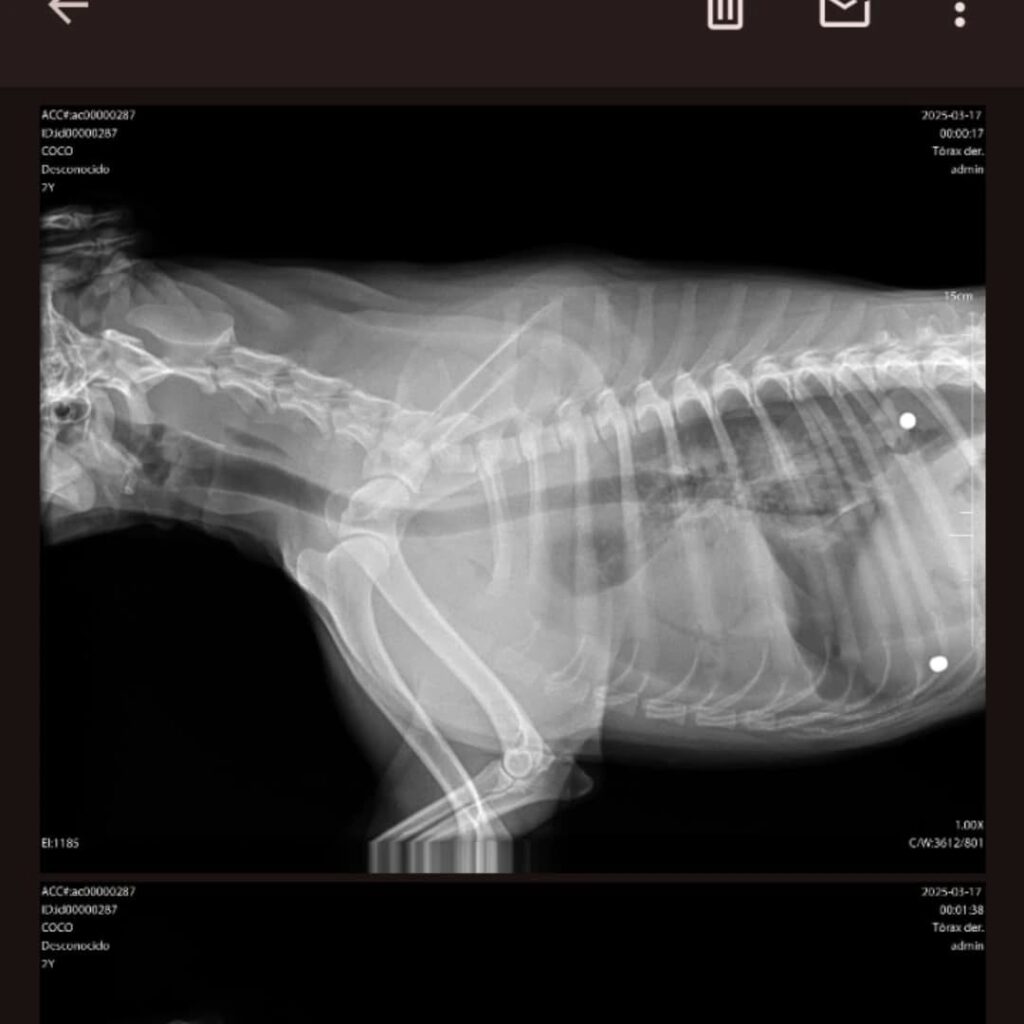

Radiografía del perrito donde se ven los proyectiles alojados

La intranquilidad y la tensión social están ganando el ánimo de los habitantes en general y Cañuelas no es ajena a esta situación. Particularmente en el barrio Libertad se están repitiendo hechos violentos. Este domingo por la noche Brenda dejó la casa de su madre en Rodríguez al 400 como lo hace siempre. Minutos después de llegar a su casa recibe el aviso de la Sra. diciéndole que habían apedreado a «Coqui», uno de sus dos macotas caninas. Al regresar al barrio Brenda toma al perrito y lo trasladan a una veterinaria de guardia en Ezeiza donde, radiografía de por medio, le confirman que no fueron piedras sino proyectiles disparados con un rifle. Uno de los mismos estaba alojado en el pulmón del perrito. Para su atención quedó internado. A las 7.10 de la mañana del lunes les avisan que el pobre animalito había muerto.